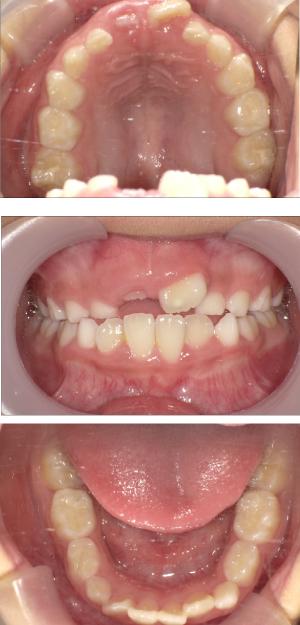

なぜ、歯並びに問題のあるお子さんが増えてきているのでしょうか?

それは現代の子どもたちの生活習慣に影響が隠れています。

バイオブロック矯正の考え方は歯並びが悪くなる原因にアプローチする治療法になります。

舌の位置や口呼吸から乱れてしまった下顎の後退を正し、顎顔面が本来あるべき位置へと誘導させていく治療です。